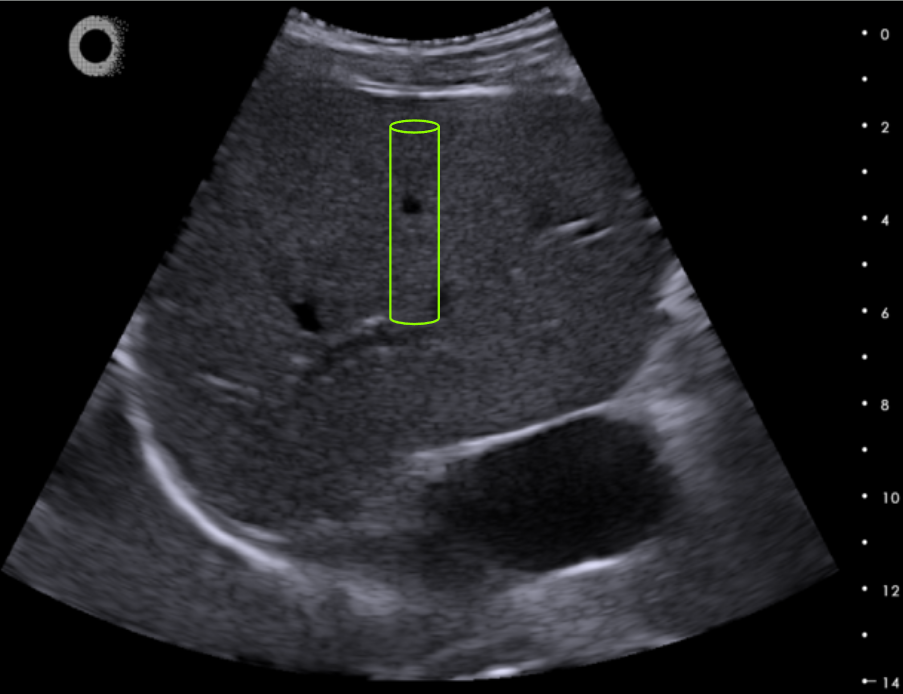

Image guidance builds confidence between operator and physician interpreting results and making clinical decisions.

The advanced features of the Hepatoscope enable broad liver disease assessment across care settings: ultraportability, 50 Hz mechanical transient elastography, ultrafast imaging (real-time stiffness imaging), B-mode image.

• Conventional ultrasound imaging to use as image guidance

• Usable by novice and expert operators

The large regions of interest ensure increased accuracy of results, critical for system-level quality control.